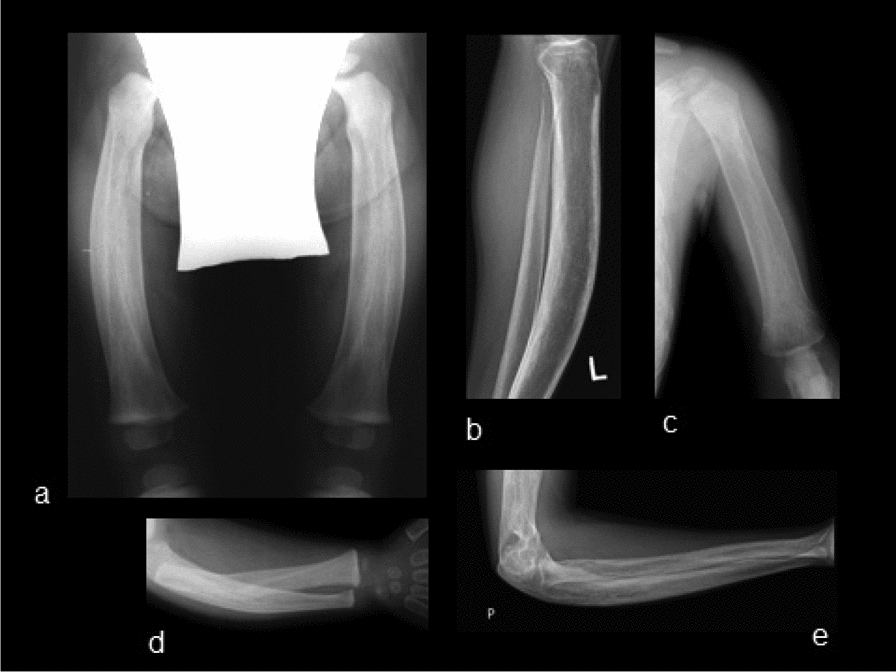

Methods and results: We report the first case of JPD diagnosed in the Czech Republic, who presented with a mild phenotype of this disease. The first bone fractures, appeared at 3 years of age. Other clinical manifestations included typical skeletal deformities, macrocephaly, arched chest, lower extremity valgosity, lateral bowing of the thighs, and anterior bowing of the shins. Minor mixed hearing impairment, angioid stripes of the choroidea, and temporary immunodeficiency were present among extra-skeletal findings. Sanger sequencing was performed on both the patient and the parents to test for the presence of TNFRSF11B sequence variants. Molecular genetic analysis showed unique compound heterozygous sequence variants in TNFRSF11B: a paternally inherited variant c.30 + 5G > A, p.(?) and a maternally inherited variant c.329G > T, p.(Gly110Val). Both of the variants were analyzed by several in silico predictive tools indicating, for their strongly supported pathogenicity according to American College of Medical Genetics and Genomics standards. Furthermore, we present diagnostic findings, their treatment, and follow-up care.